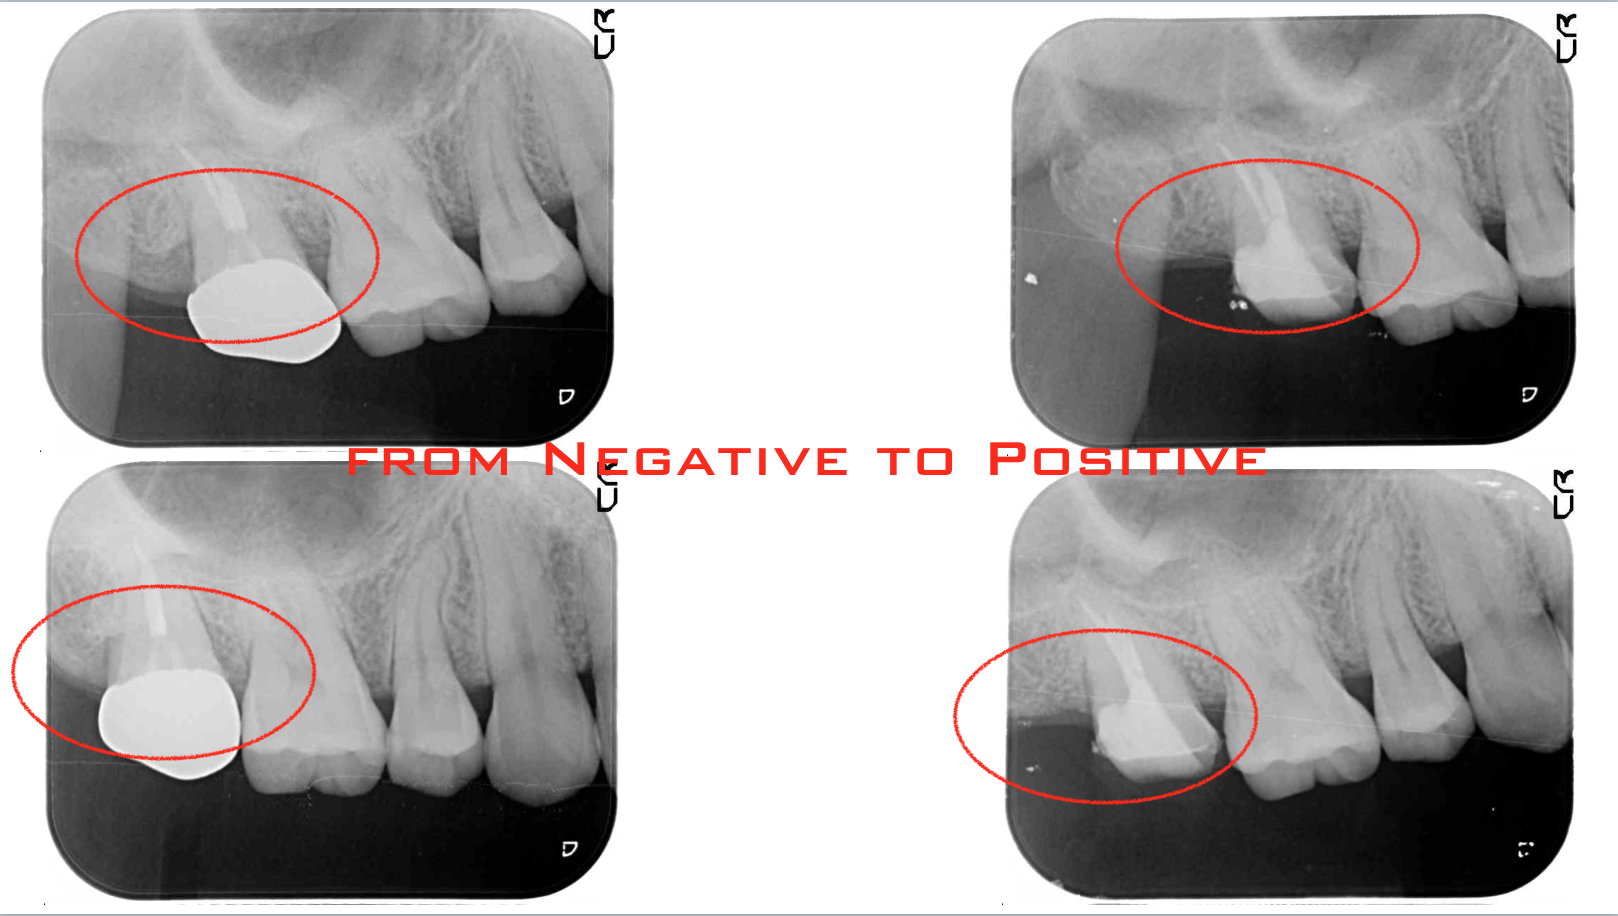

歯周病 2018.10.26 中等度歯周病に対する歯周外科治療わかりやすく説明 グラグラになるまで放置しないで! 先ずは上の写真をご覧ください。向かって左が治療前、右が治療後です。赤丸で囲んだ部分の違いがわかりますか? 左にあった骨の...